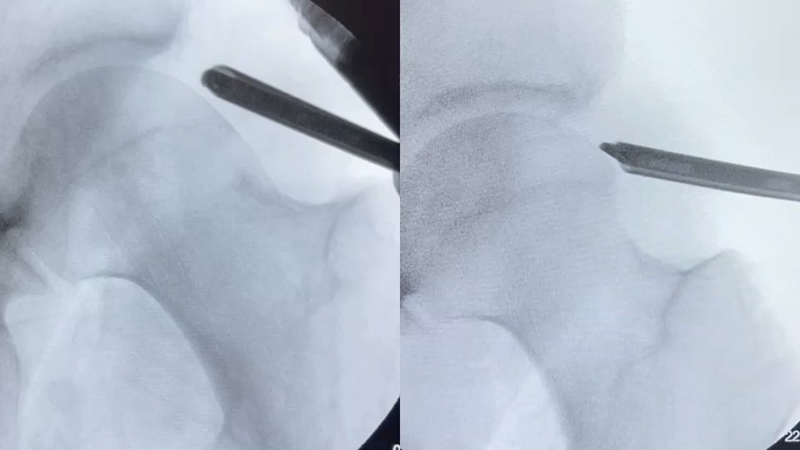

Arthroscopic surgery is a minimally invasive procedure performed using small incisions and specialized instruments. It allows Dr. Shane J. Nho to visualize the inside of the hip joint and address various abnormalities, including:

- Impingement Correction: Removal of bony impingement or reshaping of the hip joint structures to alleviate impingement and prevent further damage.